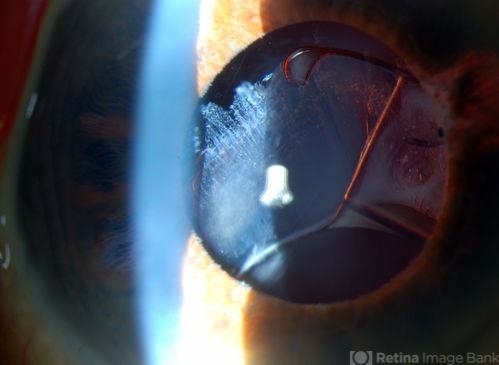

- SubluxatedCrystallineIOLwithPseudoexfoliation

- dislocated crystalline lens, pseudoexfoliation of lens capsule

- 82-year-old male came in with blurriness on the bottom half of his vision. Patient's VA was 20/25. Slit lamp examination shows subluxated crystalline lens inferiorily. Pseudoexfoliation debris superiorly at 10 o'clock with no vitreous present in the anterior chamber. Patient scheduled for surgery for CE IOL in the right eye.